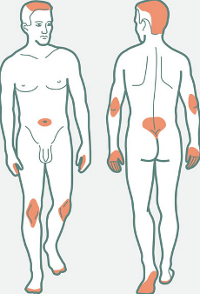

- Plaque psoriasis symptoms are red rough plaques that are generally scaly. The plaques may appear on various parts of a body, though the most common locations are knees, elbows and trunk. Sometimes the lesions may be found on genitals, between or under breasts or buttocks and on scalp. Generally, the plaques are itchy or even painful if the skin is too dry and when it cracks.

- Red patches in such areas as genitals and armpits are typical inverse psoriasis symptoms. Such patches also appear between or under breasts or in some other places that may be sweating. Overweight people are more predisposed to this disease.

- Itchy red patches with puss-filled blisters that appear in various body parts, including hands and feet in combination with fever and fatigue may be pustular psoriasis symptoms. The disease develops very quickly and the blisters may grow and temporarily disappear, but then they occur again and again. This type of psoriasis is quite rare.